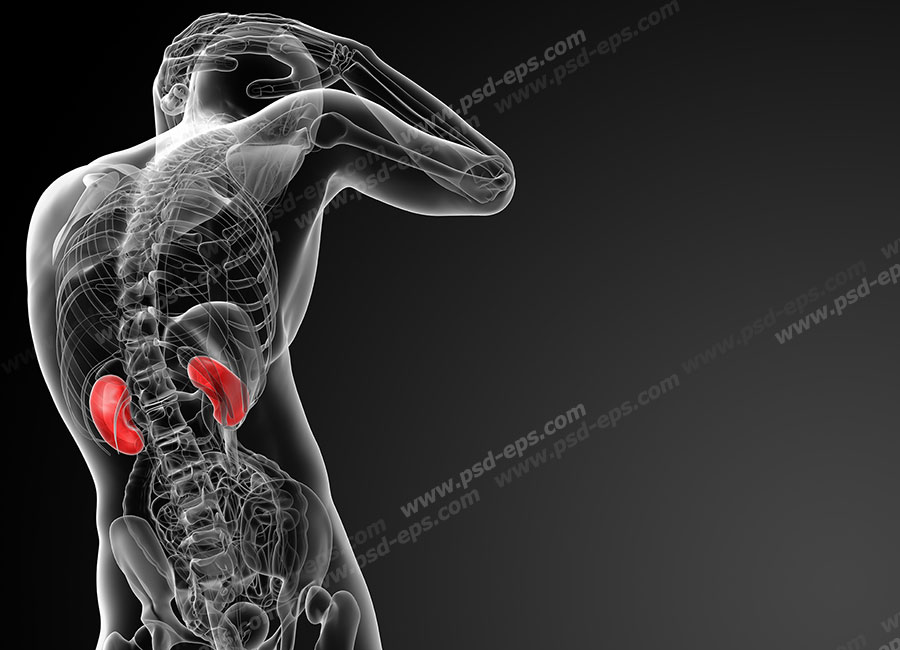

عکس کلیه در بدن. اگر پشت یا پهلوی شما آسیب ببیند مثل برخورد ضربه ممکن است فکر کنید که کلیه هایتان درد می کنند. مقدار و نسبت ترکیب این اخلاط در بدن هر شخصی و در اندامهای. کلیه گ رده ها1 از اندام های درونی بدن انسان به صورت یک جفت عضو لوبیایی شکل در طرفین ستون فقرات روی جدار پشتی شکم و بیرون از حفره صفاق قرار دارند. ک لیه ق لوه میز یا گ رده یکی از اندام های درونی بدن انسان و برخی دیگر از جانداران است.

وظایف کلیه ها در بدن. و دخالت این چهار مایع را در کلیه حالات بدنی. شکل زیر عکس واقعی کلیه انسان را نشان می دهد. اگر عملکرد آن ها کم شود نیاز به دیالیز پیدا می کنند.